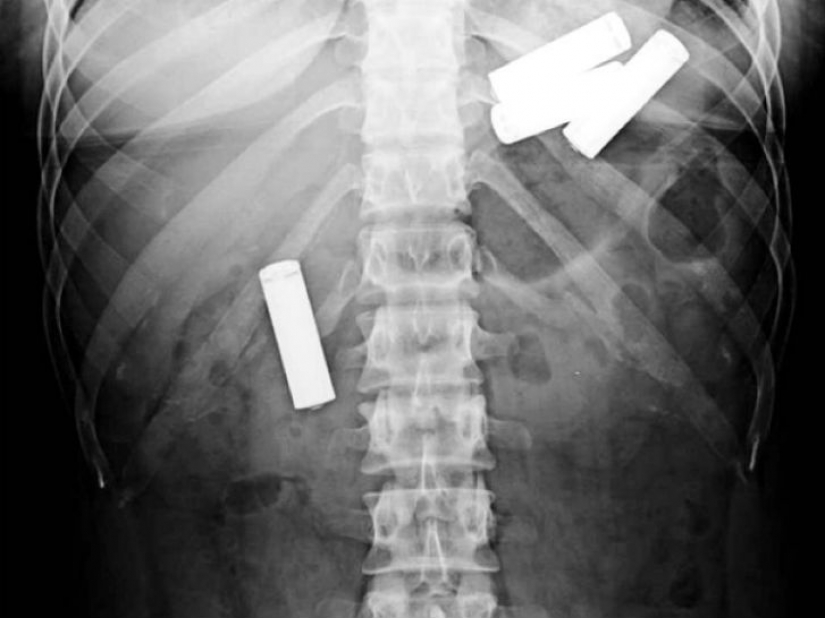

Aquí las baterías, tal vez son sólo niños. De rayos X de 13 meses de vida del bebé.

Y es que parece que el hombre que se tragó una gran cantidad de medicamentos para llevar a su contrabando a través de la frontera.